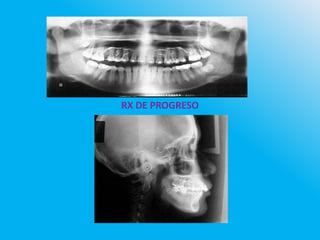

RX DE PROGRESO